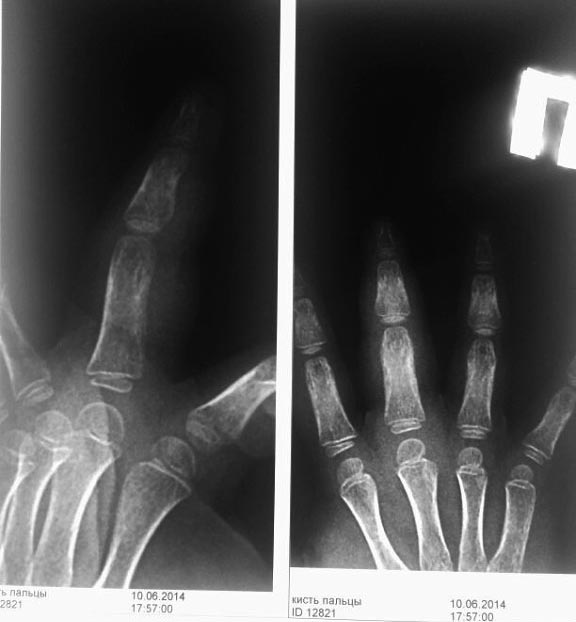

Ребенок 4 года в конце апреля прищемил палец стулом. Через 2 недели палец стал опухать. Через месяц в июне они пришли, сделали рентген - ничего нет. Они ничего не делали (то мазали, то не мазали разными мазями). В июле опять пришли с таким же пальцем ни чуть не изменился. Сделали рентген - какая-то реакция надкостницы слабовыраженная у основания основной фаланги 3п кисти. Узи сделали - типа гематома м/тк после травмы. Все посмотрели (хирурги, рентгенологи и травматологи). Все дружно решили - гематома, лимфостаз, надо компрессики, массажи, ванночки, помазюкать и все пройдет. Пришли на этой неделе (5 месяцев после травмы) - всё то же, не прошло, палец только толще. Рентген - какая-то штука выросла у основной фаланги и лезет на среднюю. На узи усиленный кровоток в сухожилии сгибателя и отек сухожильного влагалища на всем протяжении. Сделали ОАК - без патологии, б/х (о.белок, билирубин, аст, алт, амилаза, мочевина, креатинин, К, Na, Ca) - без патологии, на ЩФ - нет реактива в лаборатории. Палец не болит, сгибается, цвет кожи не особо изменен. Отек плотный. Движения в полном объёме, только в межфаланг.суст чуть ограничены из-за сильного отека. Ребенка этот палец совсем не беспокоит. Что это может быть? и какие дополнительные обследования необходимы?

второй снимок через 2 месяца после травмы. И снимок через 5 месяцев прямая проекция. Боковая проекция через 5 мес указана в самом начале

А что значит лучьше? Боли нет. Функция полная. Был перелом. Он сросся. Это хорощо видно. Имеется костная мозоль (или периостит если угодно). Со временем, лет через 5- 6 все будет о к.